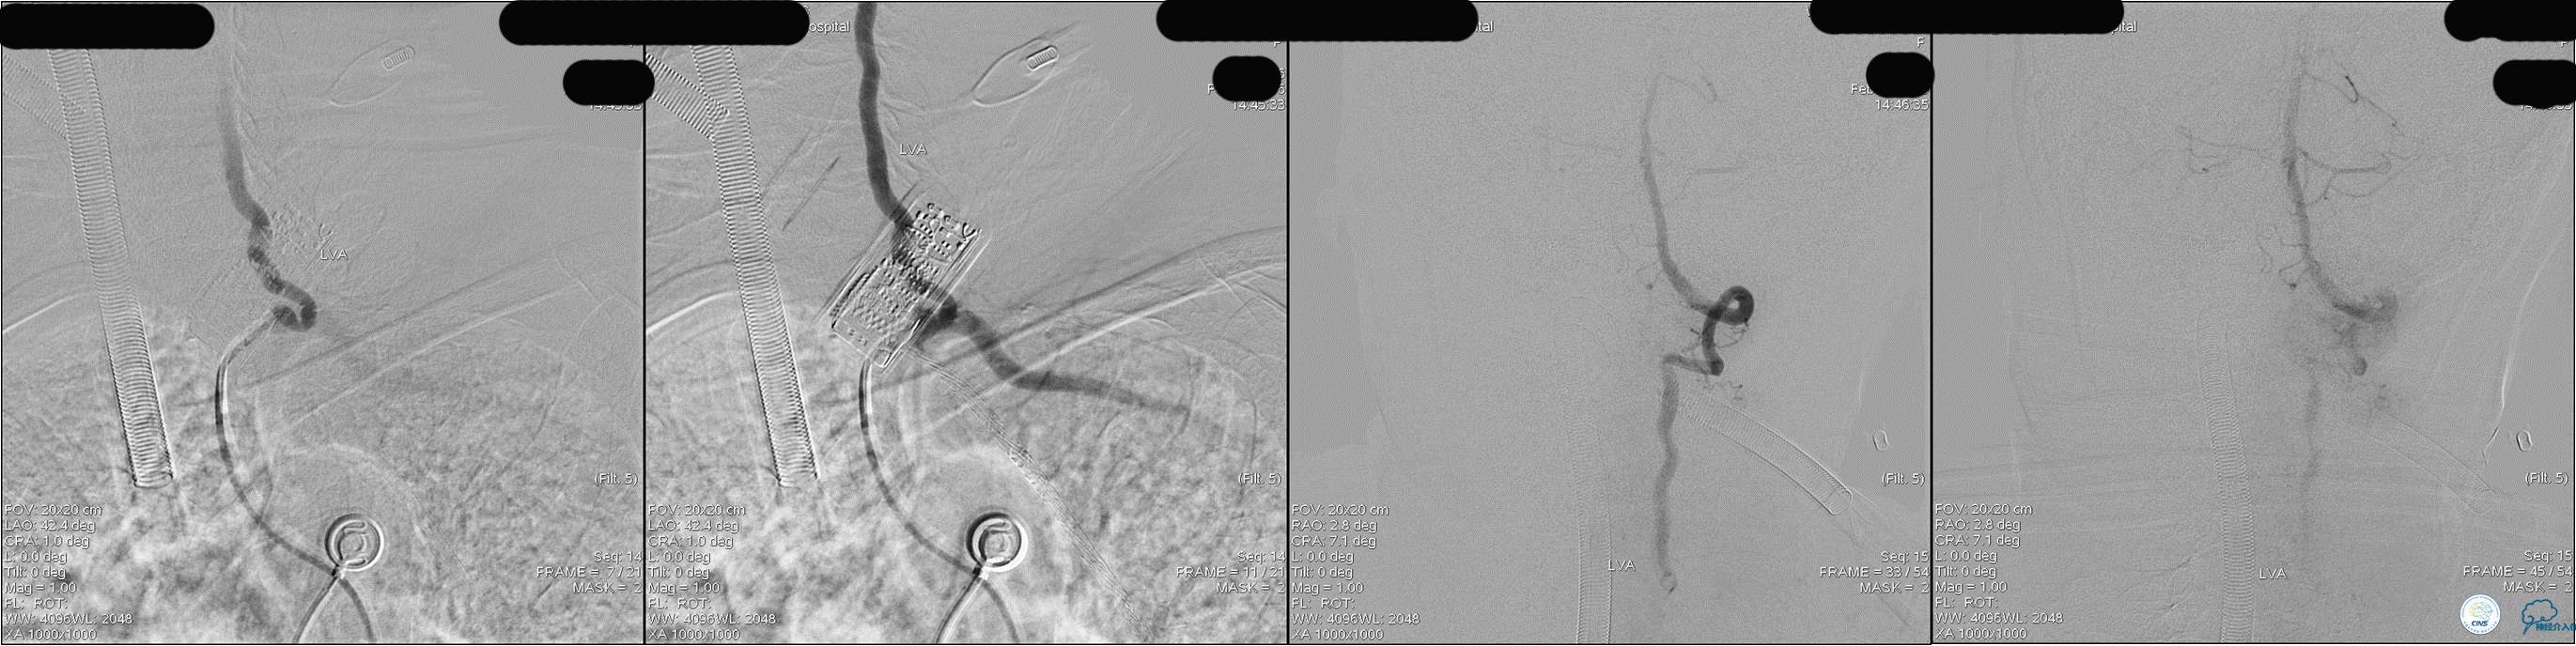

》DSA资料(经桡动脉,5F导引导管)

》DSA资料(右侧椎动脉)

》DSA资料(前2次取栓,未取出,soli 4-20)

》DSA资料(第3次取栓)